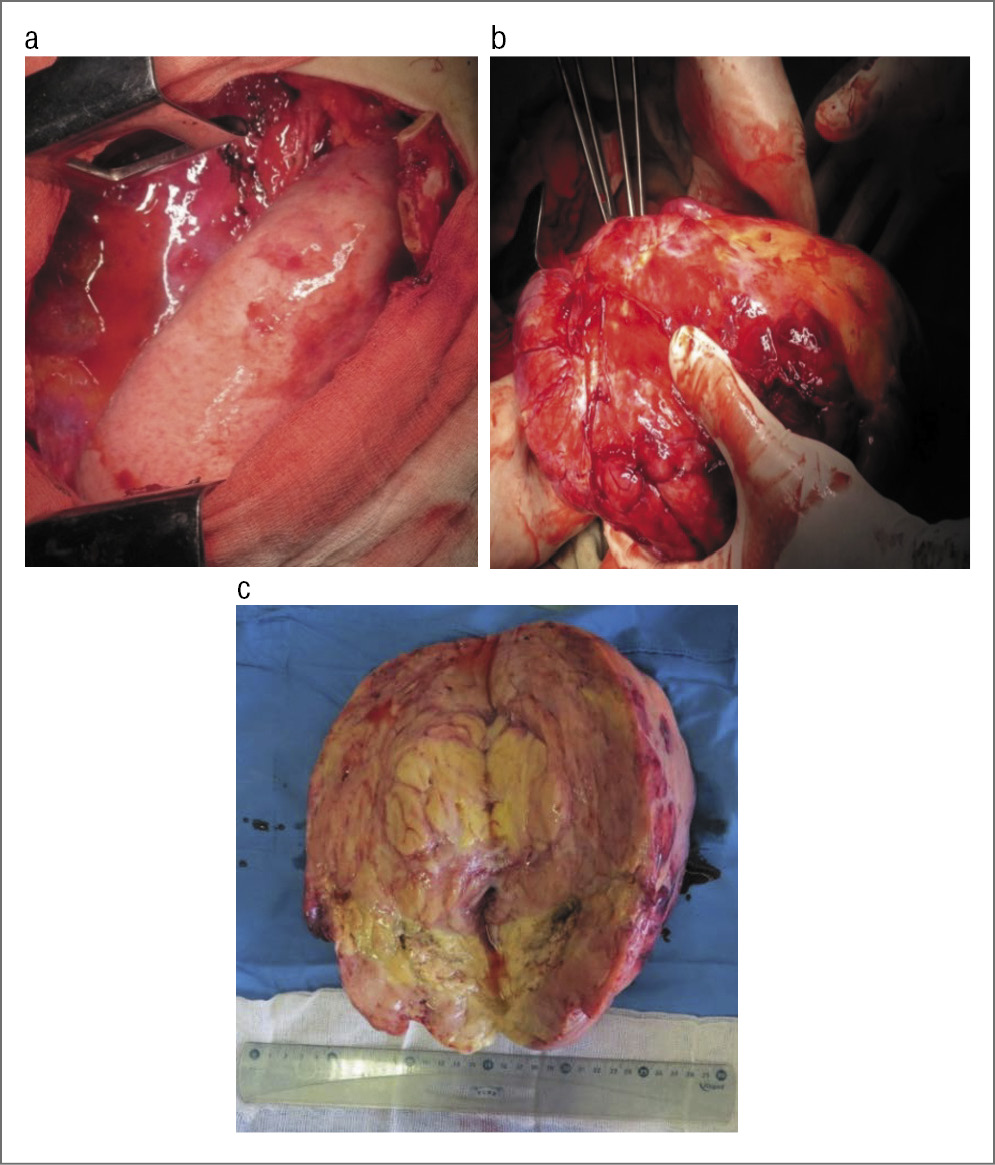

С учетом данных КТ-исследования с контрастированием определен вариант оперативного вмешательства: торактомия справа, удаление опухоли заднего средостения (рис. 8, a–c).

Рис. 8. а, b – ход операции; c – опухоль (невринома).